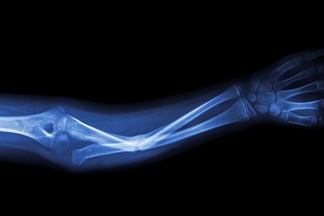

In Western societies, fragility fractures are increasing in absolute numbers and are associated with the increase in life expectancy. The WHO published in 2008 a tool to properly identify the population’s increased risk of fragility fracture and prioritise preventative actions among the most vulnerable groups. This thesis proposes a calibration of this tool for the Spanish female population which would reduce tests and pharmacological treatment and, therefore, health expenditure.

Fragility fractures in Spain, as in other Western societies, are increasing in absolute numbers, associated with the increase in life expectancy and it is necessary to properly identify the population at risk of fragility fracture and to prioritize preventive actions on the most vulnerable groups. In 2008, the WHO published the FRAX tool for a growing number of countries. This is an online algorithm to calculate the absolute risk of fracture for 10 years, but it needs some adjustments or calibrations in each country for validation.

Top left figure by iStockphoto/stockdevil.